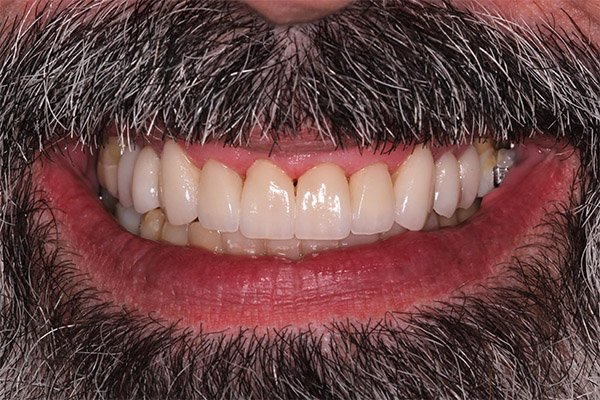

Antes e Depois

IMAGENS REAIS – sem qualquer tipo de manipulação!